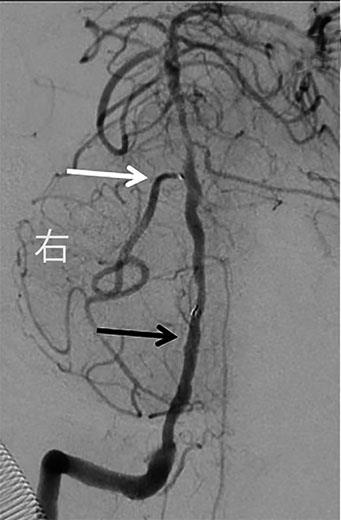

• 挽救性支架植入对取栓困难的脑动脉栓塞开通效果

2022, 47(7):779-783. DOI: 10.13406/j.cnki.cyxb.003067

摘要:目的 探究急性脑栓塞取栓失败和神经介入术中发生医源性脑动脉栓塞后补救性支架植入术的开通效果。方法 回顾性分析2020年1月至2021年11月上海交通大学医学院附属第九人民医院6例脑栓塞取栓失败和4例医源性颅内中远端动脉栓塞、接受补救性支架植入术的患者临床信息,总结患者术后血管开通情况、术后24 h 支架内血流通畅情况、出血转化和预后等情况。结果 6例急性脑栓塞取栓失败,补救性支架植入后闭塞血管全部开通(modified thrombosis in cerebral infarction score,mTICI 2b~3),术后3例出血转化(1例PH2型,2例HI2型),术后24 h支架内血流通畅5例(83%),1例未行血管造影复查;3例患者住院期间死亡。4例医源性中远端动脉闭塞中,1例为原发病为椎基底动脉高度狭窄,支架置入术中发生右侧小脑前下动脉闭塞,补救性支架置入后完全开通,术后24 h复查所有支架通畅,无脑出血,3个月预后良好,改良Rankin量表(modified Rankin score,mRS)评分1分;3例原发病为大脑中动脉栓塞,取栓术中出现同侧大脑前动脉分支闭塞,补救性支架植入后完全开通,其中1例术后24 h头颅计算机体层血管成像(computed tomography angiography,CTA)可见支架通畅,合并片状出血转化(HI2型),2例因为病重未行血管复查。结论 补救性支架植入可以快速开通取栓失败以及医源性中远端动脉的栓塞,但是疗效和安全性需进一步研究。